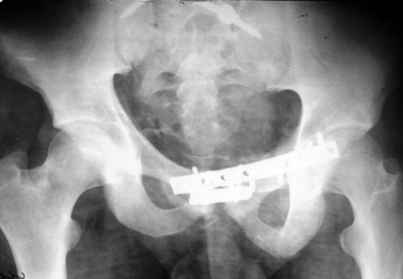

Уважаемые коллеги! 27 июля 2006г. представлял на форум больного со сложным застарелым переломом таза. Сейчас провели контрольное обследование.

Результат представляю в картинках.

Фиксация сзади выполнена системой "Силует" фирмы "Зиммер", предназначенной для транспедикулярной стабилизации позвоночника. Юрий Алексеевич Булахтин

Клинически пациента ничего не беспокоит, служит он в МЧС пожарным.

Думаю. что если расспросить более детально, то жалобы все же обнаружатся. Pohlemann и сотоварищи не получили ни одного отличного функционального результата при резидуальном смещении в задних отделах более 10 мм (здесь явно больше). Действительно на функциональных фото все выглядит неплохо, поздравляю.